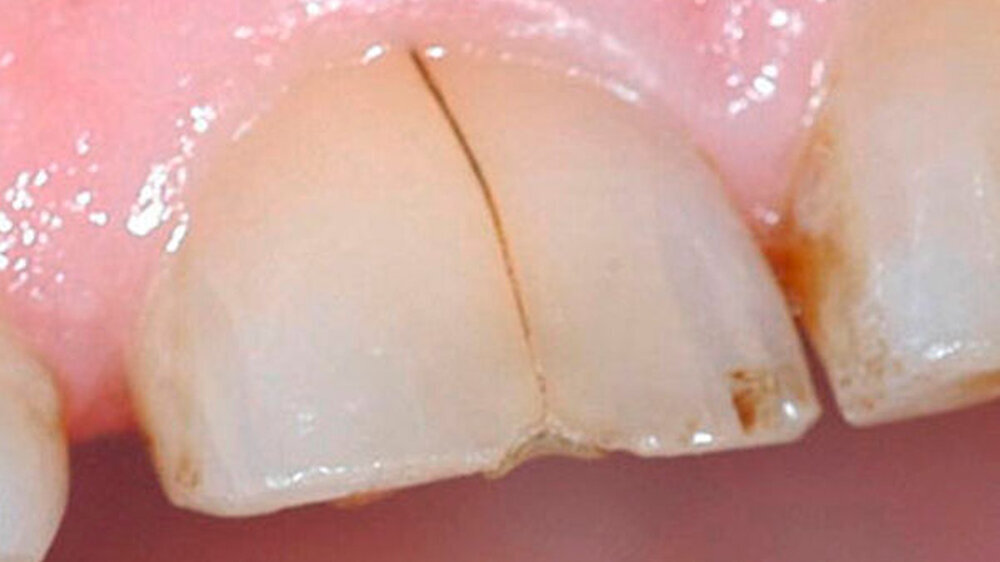

Bei der Vorstellung in der Poliklinik zeigte sich klinisch eine Schmelzfraktur auf der bukkalen Fläche des Zahns 11 (Abbildung 1). Die Messung der Taschensondierungstiefe (TST) ergab an dieser Stelle lokal begrenzt einen Wert von 7 mm (Abbildung 2). An allen übrigen Messpunkten lag eine physiologische TST von 3 mm vor.